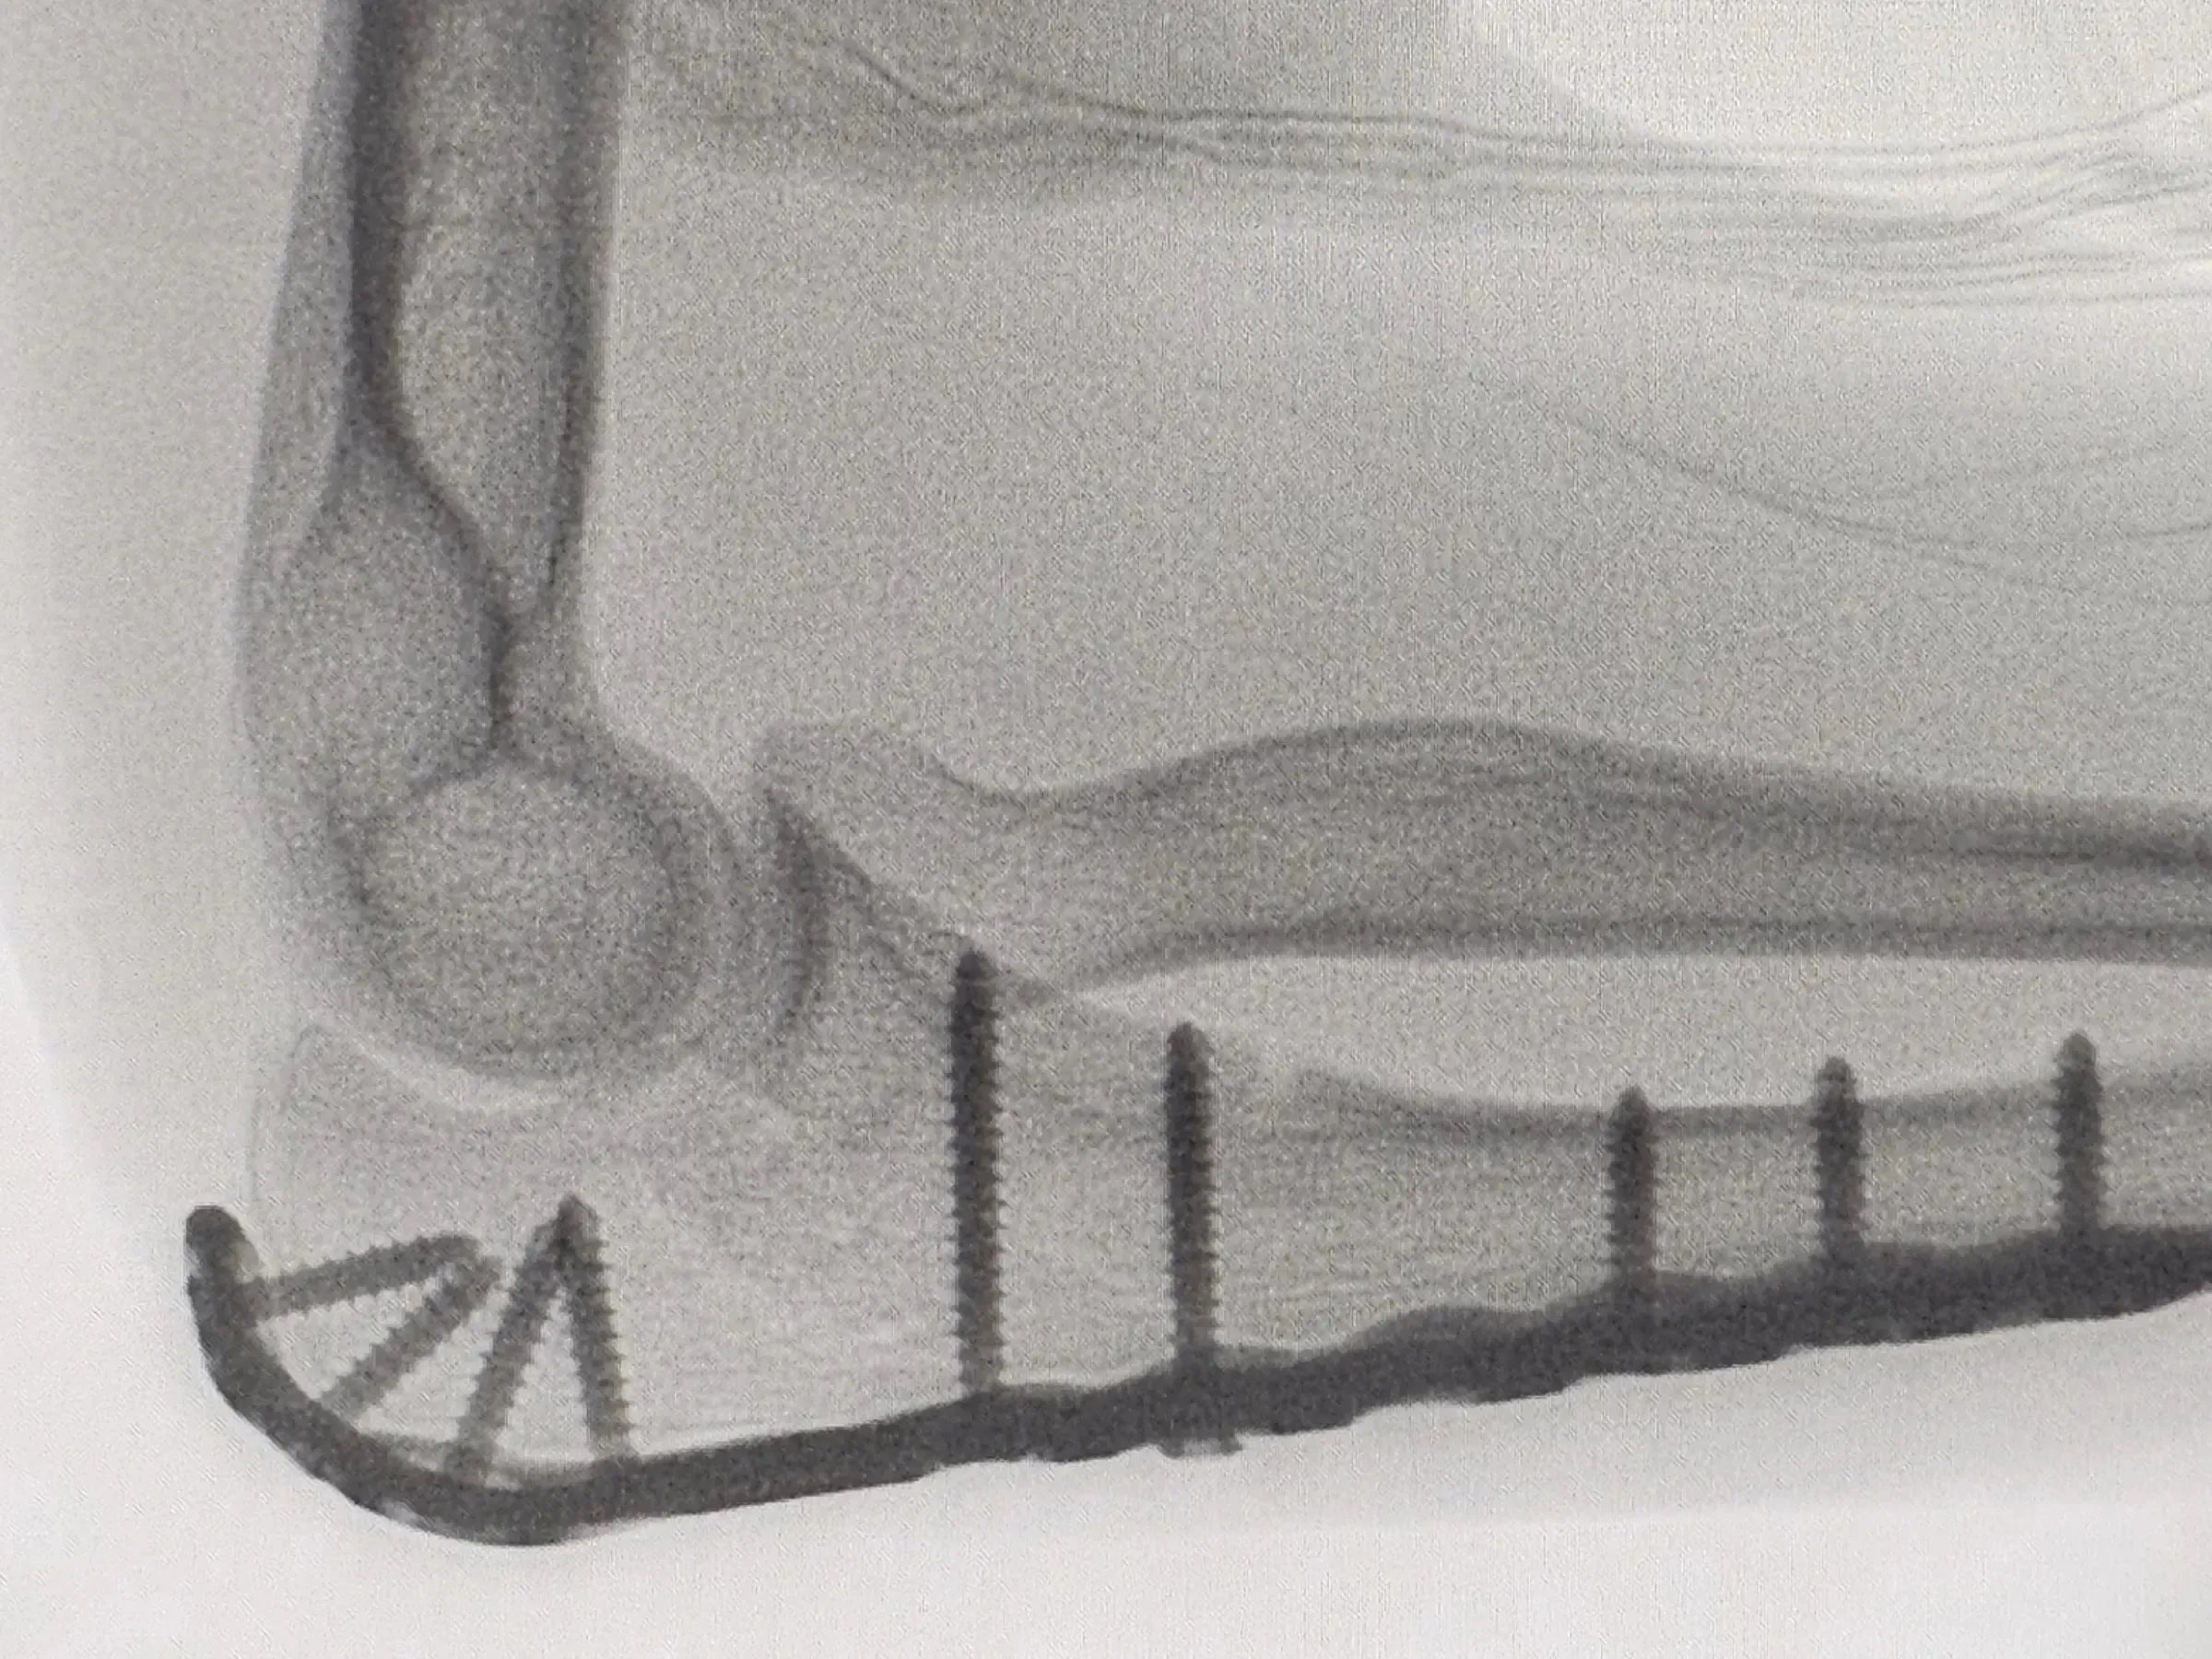

Osteossíntese Minimamente Invasiva de Fratura de Olécrano

Osteossíntese do olécrano: cirurgia de precisão para preservar a função articular em pacientes jovens.

Domine a osteossíntese minimamente invasiva de fraturas articulares do olécrano, importante para a preservação da função articular a longo prazo em pacientes jovens. Este treinamento detalha uma abordagem cirúrgica que visa minimizar o trauma tecidual, otimizar a estética e permitir mobilidade precoce no pós-operatório, garantindo redução anatômica e fixação estável.

- Fixação da Placa: Início com parafuso dinâmico excêntrico para compressão, seguido de fixação provisória intramedular. Substituição por parafusos bloqueados subcondrais para maior resistência. Sistema de broca agiliza o procedimento.

- Parafusos Percutâneos: Inserção distal por mini-acesso e parafuso intermediário por incisão percutânea guiada por palpação. Finalização com parafusos bloqueados.

- Fechamento e Resultado Final: Fechamento anatômico de periósteo e pele, guiado por marcas dermográficas. Técnica minimamente invasiva preserva a musculatura e permite mobilidade precoce no pós-operatório.